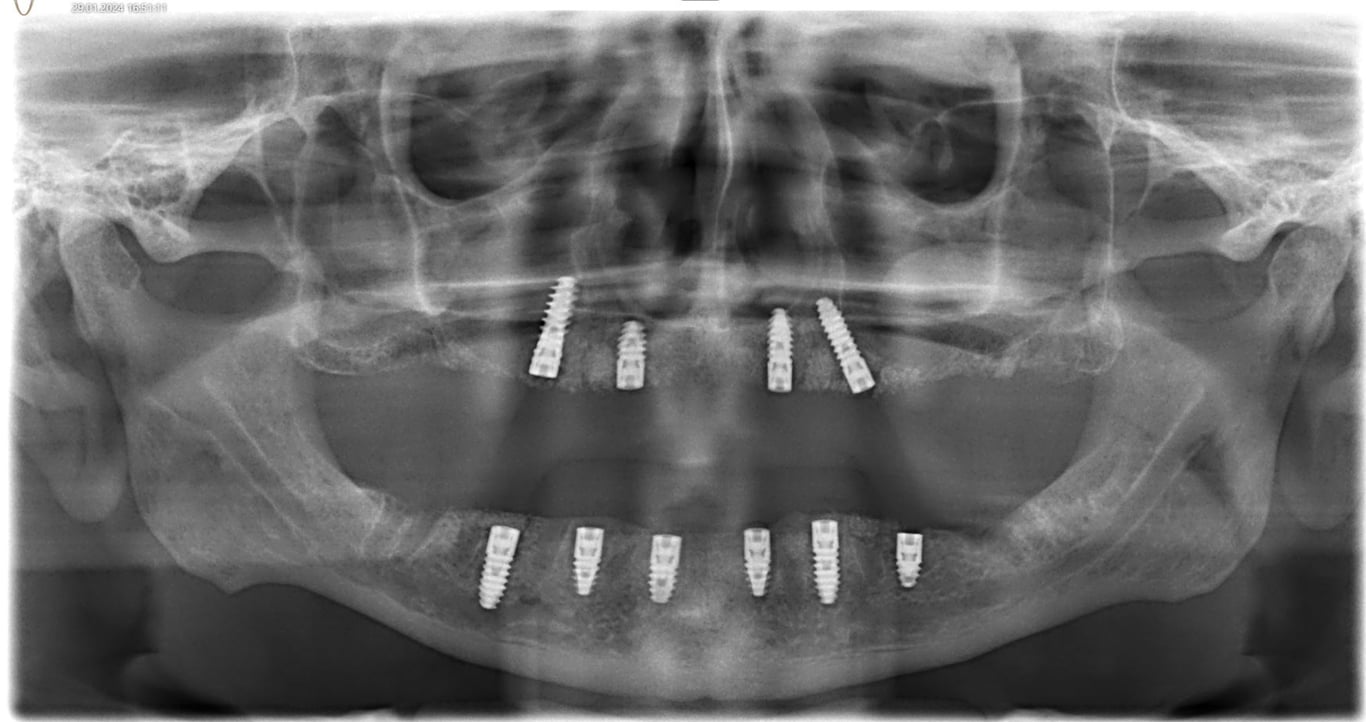

Lisa from USA: Missing all teeth

After: All on 4 upper and lower jaws at Amaris Dental Clinic